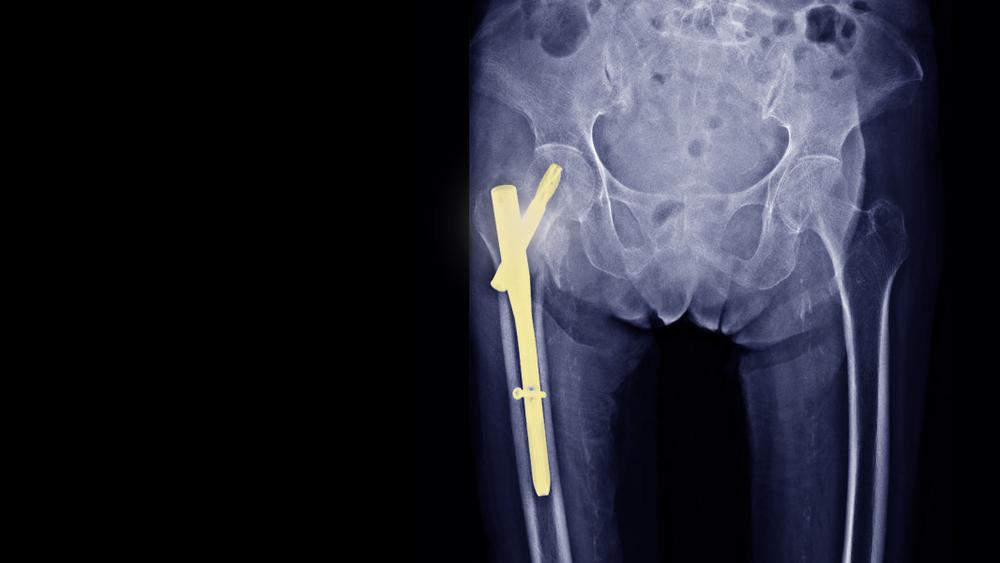

Pen adalah alat pendukung seperti pelat, sekrup, batang, dan kabel yang terbuat dari stainless steel atau titanium. Alat ini biasanya akan dokter gunakan pada operasi tulang, seperti:

- membantu tulang yang patah berada pada posisinya saat masa pemulihan,

- menyatukan tulang secara permanen (arthrodesis),

- mengubah bentuk tulang (osteotomy).

Pada saat itu, dokter akan mengangkat pen melalui sayatan yang sama ketika dokter bedah pertama kali memasukkan pen ke dalam tubuh Anda.

Biasanya, dokter akan lebih kesulitan menemukan pen jenis sekrup kecil atau kawat. Oleh sebab itu, dokter akan membuat sayatan lebih besar dan menggunakan bantuan kamera X-ray.

Selain itu, dokter mungkin juga akan kesulitan untuk menemukan pen yang tertutup oleh jaringan parut atau tulang meski pen memiliki ukuran yang lebih besar.